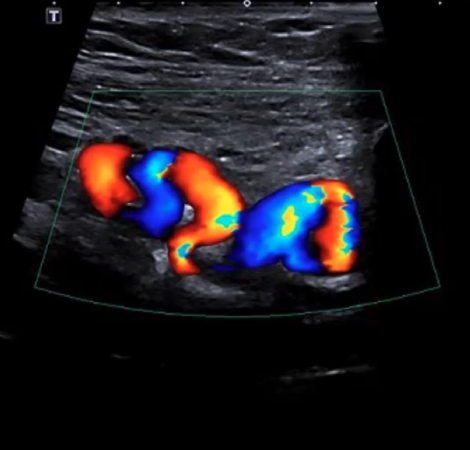

Το ποσοστό των γυναικών που έχουν συμπτώματα πυελικής συμφόρησης μπορεί να αυξηθεί μετά από τη 2η εγκυμοσύνη. Στα γεννητικά όργανα και το περίνεο μπορεί να εμφανιστούν διατεταγμένες φλέβες, κιρσοί και πόνος μη περιόδου στην πύελο, καθώς και αίσθημα συνεχομένου βάρους.

Το σύνδρομο πυελικής συμφόρησης προκαλείται από την ανεπαρκή επαναφορά του φλεβικού συστήματος, αποτελώντας συνέπεια της φλεβικής στασιμότητας. Εξαιτίας της έλλειψης ροής του αίματος στις φλέβες της περιοχής του πελβικού ιστού, όπως στα γεννητικά όργανα, την ουροδόχο κύστη και το έντερο, το αίμα αντιμετωπίζει δυσκολία στην επαναφορά του, προκαλώντας πιθανώς την εμφάνιση κιρσών στα γεννητικά όργα και τα κάτω άκρα.